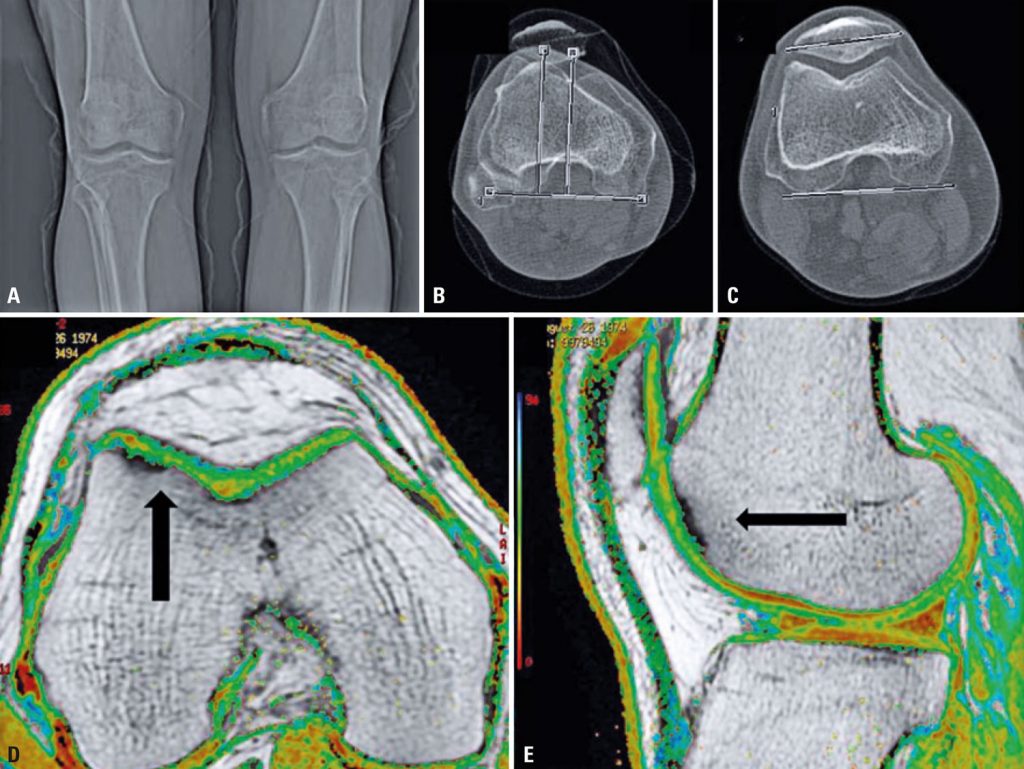

To describe a case of autologous chondrocyte implantation after cell culture contamination by Mycoplasma pneumoniae and the measures taken to successfully complete cell therapy in a patient with focal chondral lesion. A 45-year-old male patient, complaining of chronic pain on the knee and no history of trauma. He had a chondral lesion in the trochlear region of the femur and clinical tests compatible with pain in the anterior compartment of the knee. Conservative treatment failed to alleviate symptoms. Surgical treatment was indicated, but due to the size of the lesion, membrane-assisted autologous chondrocyte implantation was the technique of choice. Cartilage biopsies were collected from the intercondylar region of the distal femur. After isolation, chondrocytes were expanded ex vivo in a trained laboratory, for three weeks, and seeded onto a commercially available collagen membrane prior to implantation in the knee. Two days before surgery, a cell culture sample tested positive for Mycoplasma pneumoniae. The source of contamination was found to be autologous blood serum, extracted from the patient´s peripheral vein, and used to supplement the cell culture medium. After treating the patient with antibiotics, all procedures were repeated and the new final cell product, free from contaminants, was successfully implanted. We discuss the strategies available to deal with this situation, and describe the results of this particular case, which led to modifications in the autologous chondrocyte implant protocol.